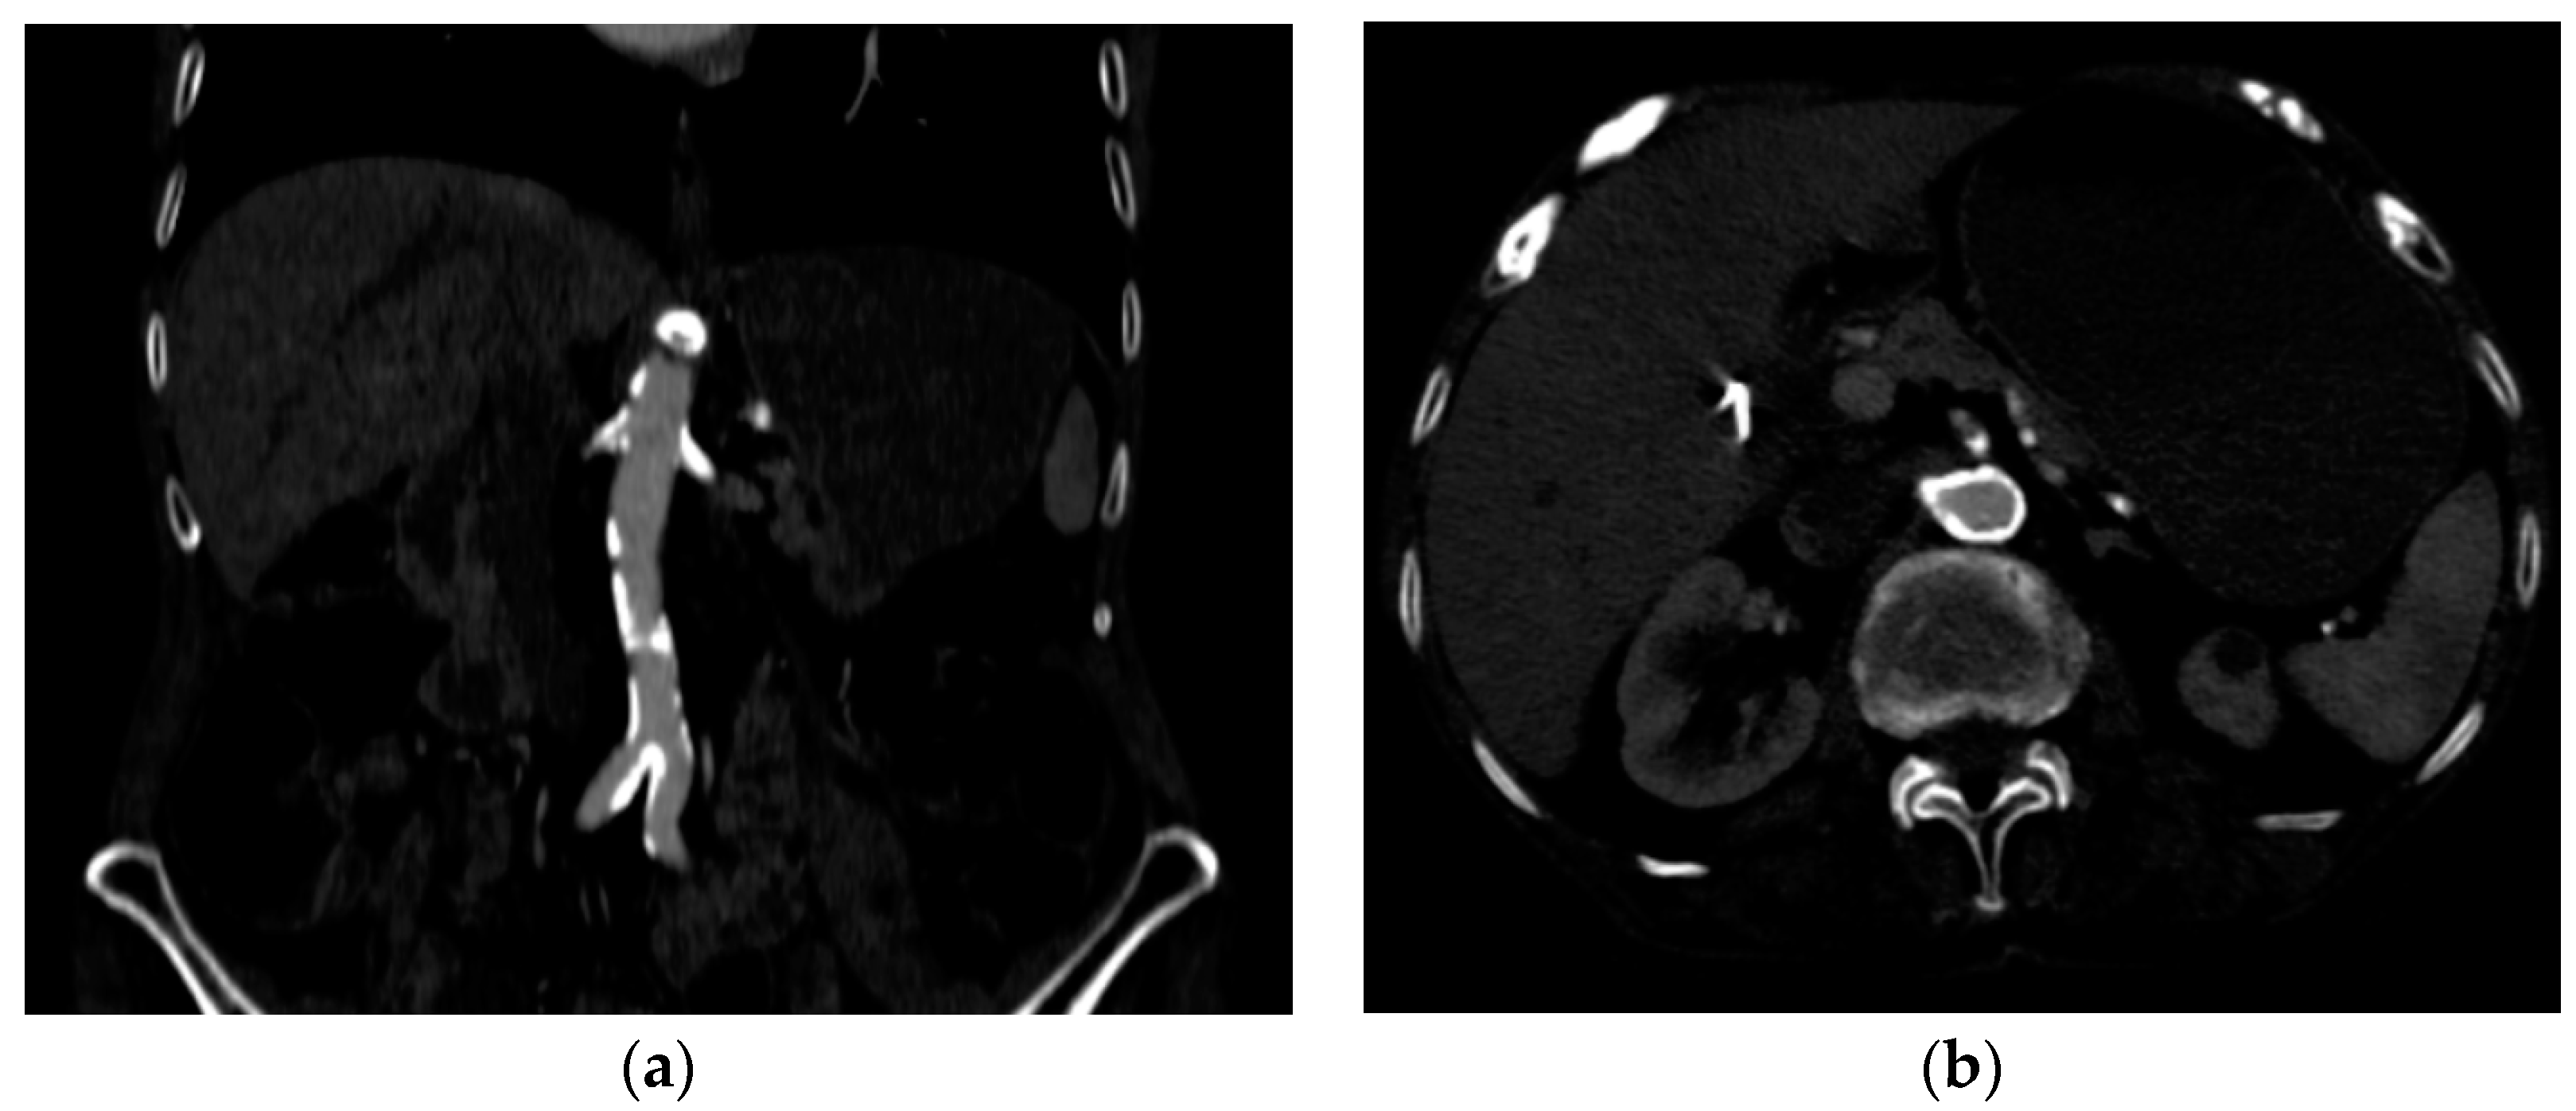

2. Case Presentation